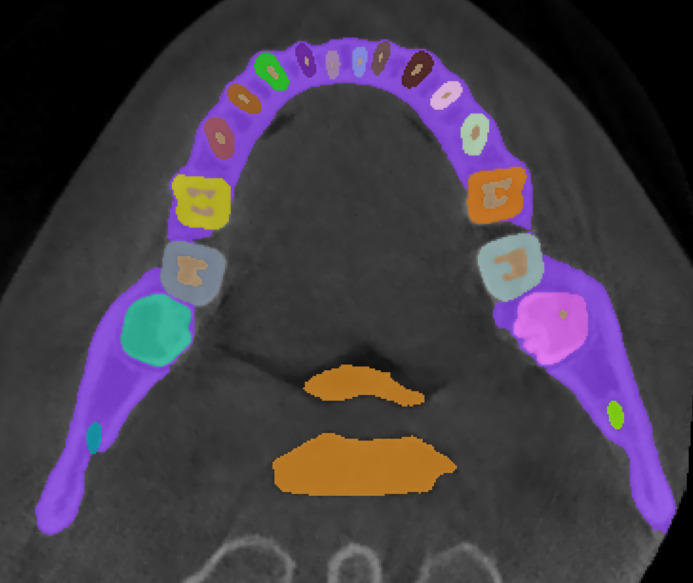

3.2 Qualitative Results

Fig.˜2 visualizes the qualitative comparison between the ground truth and our model’s predictions of the scans with the highest and lowest Dice score in the validation set, in the top and bottom rows, respectively. We observe that in most cases, U-Mamba2 produces precise segmentation predictions, showcasing the effectiveness of incorporating dental domain knowledge into the model design. Furthermore, we observe that U-Mamba2 can accurately localize the three tiny structures (ILN), producing visually acceptable segmentations. In the worst-case scenario, although the scan is imperfect due to image artifacts caused by metallic objects, false positives are primarily confined around the image edge or confusion between the actual tooth and the crown or implant, underscoring U-Mamba2’s robustness under noisy conditions.